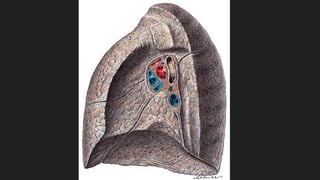

PULMONES

 Son órganos pares en los que se realiza la hematosis

 FORMA: Semicónica

- Vértice, sobresale por el orificio superior del tórax y ocupa la base del cuello.

- Base, es cóncava y semilunar, se apoya en el diafragma. La base derecha es algo más

elevada que la base izquierda.

- Cara medial, se encuentra el Hilio Pulmonar.

- Cisuras, son hendiduras que separan porciones del pulmón de forma parcial. Ambos

pulmones presentan una cisura oblícua y del derecho presenta una cisura horizontal.

Dividen al pulmón en lóbulos. El pulmón derecho presenta 3 lóbulos y el izquierdo 2.